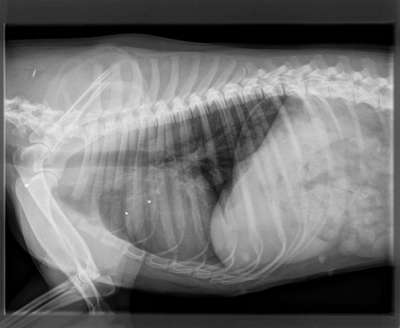

Wenn dein Hund weg ist und er am nächsten Tag vor der Tür steht. Erstmal denke ich wird jeder sowas von froh sein, wenn der Freund nach langem suchen wieder da ist. Was ist aber, wenn er schwer verletzt ist und der Tierarzt dir sagt das es eine Schußverletzung ist und es abzuwarten ist ob er es überlebt. Einer Bekannten ist es so ergangen, die Hündin ist mit ihrem Freund entwischt und stand am nächsten Tag vor der Tür. In einer OP wurde das Auge entfernt und jede Menge Blei entfernt. Es bleibt abzuwarten, ob die Hündin es überlebt, denn das Blei konnte nicht komplett entfernt werden. Eine Bleivergiftung ist tötlich. Was würdet ihr tun? Es hinnehmen oder dagegen angehen? Die Hündin hat sich nicht für Wild interessiert. Der Jäger hat genau ins Auge geschossen und ihr Rüde der hinter ihr stand hat am Ohr eine Verletzung, diese ist aber zum Glück nicht so schlimm. Ein Jäger hat leider sehr wohl das Recht zu schießen, allerdings als letzte Instanz und muß es auch auf einem Formblatt festhalten. Ich finde es widerlich und abgrundtief traurig, das ein Mensch zu so etwas fähig ist. Denn letztendlich entscheidet er als Jäger.

Leider gibt es schlechte Nachrichten..die Maus muß morgen nochmals operiert werden, da sie noch zu viel Blei im Körper hat und die Blutwerte dementsprechend sehr schlecht sind. Ich hoffe sehr auf Besserung und wünsche nur das Beste...